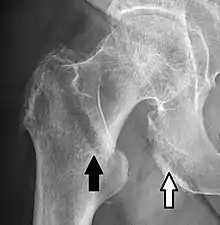

In projectional radiography, visual artifacts that can constitute disease mimics include jewelry, clothes and skin folds.[6]

A hip fracture (black arrow) next to a skin fold (white arrow).